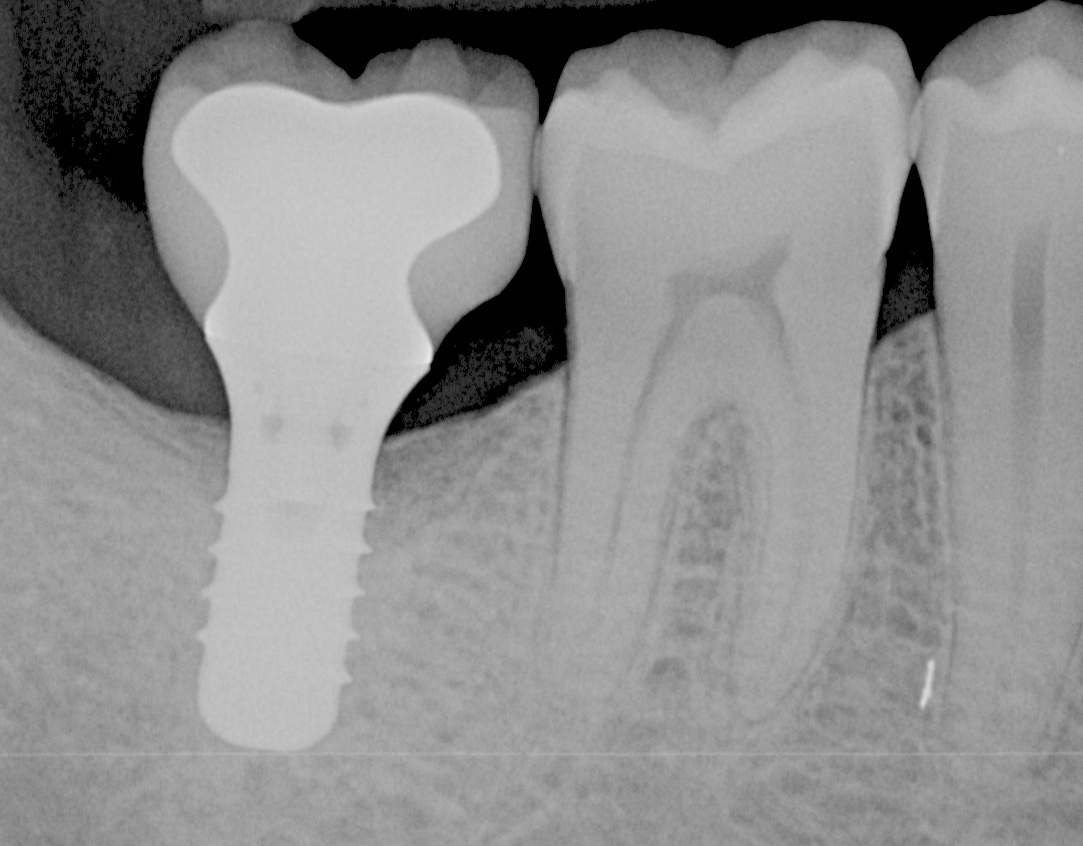

Fig 2. Radiograph of the same area. Note that there is no indication of bone loss.

Figure 2

Fig 4. A radiograph of the area suggests the advanced nature of this lesion.

Figure 4